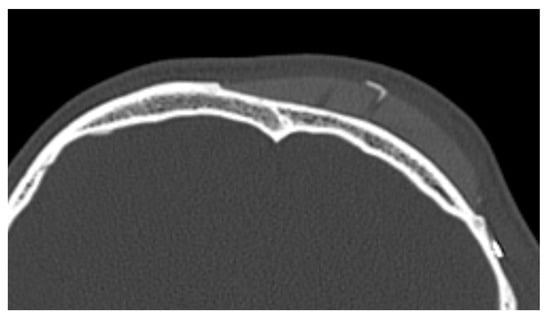

4.3. Importance of Intact and Fully Represented Periosteum

The integrity and representation of the periosteum are crucial factors in facilitating osseointegration and preventing complications associated with prosthetic implants. Indeed, regarding the periosteum reaction, what emerges from the HRCT is a non-radiologically appreciable alteration of the bone-periosteum profile, and this is a valuable sign of inert reaction of the periosteum to this material. The periosteum plays a vital role in bone healing and regeneration processes by providing a source of osteoprogenitor cells and growth factors. Preservation of the periosteum during implant surgery leads to enhanced bone formation and implant stability [52] [see Figure 4]. Conversely, damage or inadequate representation of the periosteum can impede osseointegration and increase the risk of implant failure.

A maxillo-facial surgery case: bone regeneration around the prosthesis at the level of the left mandibular angle.